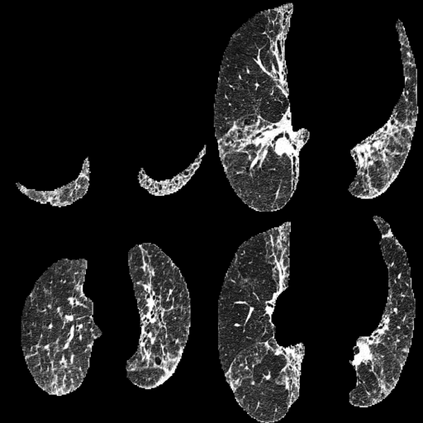

In the field of medical imaging, particularly in tasks related to early disease detection and prognosis, understanding the reasoning behind AI model predictions is imperative for assessing their reliability. Conventional explanation methods encounter challenges in identifying decisive features in medical image classifications, especially when discriminative features are subtle or not immediately evident. To address this limitation, we propose an agent model capable of generating counterfactual images that prompt different decisions when plugged into a black box model. By employing this agent model, we can uncover influential image patterns that impact the black model's final predictions. Through our methodology, we efficiently identify features that influence decisions of the deep black box. We validated our approach in the rigorous domain of medical prognosis tasks, showcasing its efficacy and potential to enhance the reliability of deep learning models in medical image classification compared to existing interpretation methods. The code will be publicly available at https://github.com/ayanglab/DiffExplainer.